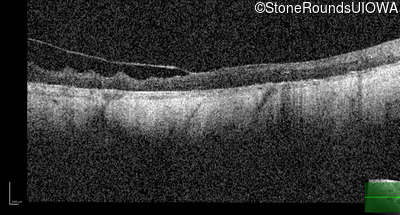

Optical Coherence Tomography - Right - Light Perception

Exemplar / OCT Stack

OCT Stack